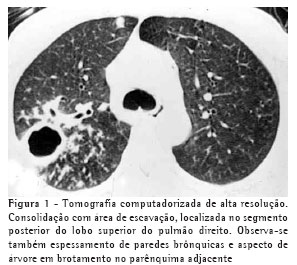

RESULTADOSO achado de imagem mais freqüente, presente nos 7 pacientes, foi consolidação de contornos mal definidos (Figuras 1, 2, 3 e 4), sendo que 5 deles tinham broncograma aéreo de permeio, principalmente na periferia da lesão. Em 3 casos, a consolidação organizava-se sob forma de massa. Em 6 dos 7 pacientes foram observadas, no interior das consolidações, áreas irregulares de escavação, múltiplas em 5 e única em 1 paciente. Em um dos casos não se observou escavação, mas ele mostrava áreas hipodensas de permeio, sugestivas de necrose (Figura 5). Apenas um dos pacientes apresentou nível líquido no interior das cavidades.

A lesão escavada predominou nos lobos superiores, sendo 4 à direita e 1 à esquerda. Em um destes pacientes, ela acometia também o lobo médio. Em 2 casos, ela ocorreu nos lobos inferiores, 1 à direita e 1 à esquerda. Em 4 casos as lesões acometiam apenas os lobos citados, sendo portanto unilaterais. Nos outros 3, atingiam também, em menor intensidade, o pulmão contralateral. Em um caso, havia também escavação de paredes relativamente finas, multisseptada, sem nível líquido, localizada no lobo médio.

Opacidades em vidro fosco foram vistas em 6 pacientes, localizadas predominantemente ao redor das lesões escavadas, não sendo, em nenhum dos casos, achado predominante.

Pequenas opacidades nodulares centrolobulares e padrão de árvore em brotamento foram vistos em 3 pacientes, com distribuição predominantemente ao redor da área de consolidação. Em 1 destes pacientes estas lesões foram encontradas também nas porções pendentes dos lobos inferiores. Nódulos do espaço aéreo, tendendo a confluência, localizados na periferia das consolidações pulmonares, foram vistos em 4 casos.

Na nossa casuística, o principal padrão de acometimento pulmonar foi o de consolidação com broncograma aéreo de permeio e escavação, presente em 6 pacientes, sendo as escavações múltiplas em 5 casos e única em 1. As consolidações tinham grandes proporções e contornos anfractuosos. Os broncogramas aéreos estavam localizados nas porções periféricas das lesões. O lobo pulmonar mais freqüentemente envolvido foi o lobo superior direito, acometido em 4 pacientes. A maioria dos trabalhos de revisão de casos confirma tais achados.(2,5) Alguns trabalhos relatam que, embora a escavação possa não estar presente no momento do diagnóstico, ela acaba por se desenvolver durante a evolução da doença.(4) Níveis líquidos no interior das escavações foram vistos em apenas um paciente na casuística estudada.

Outros achados foram as opacidades em vidro fosco, os nódulos do espaço aéreo, os pequenos nódulos de distribuição predominantemente centrolobular, e o padrão de árvore em brotamento. Eles se localizavam predominantemente ao redor das consolidações escavadas, sendo que em um dos casos também estavam presentes em ambos os lobos inferiores. Acredita-se que tal achado deva representar disseminação broncogênica da infecção.